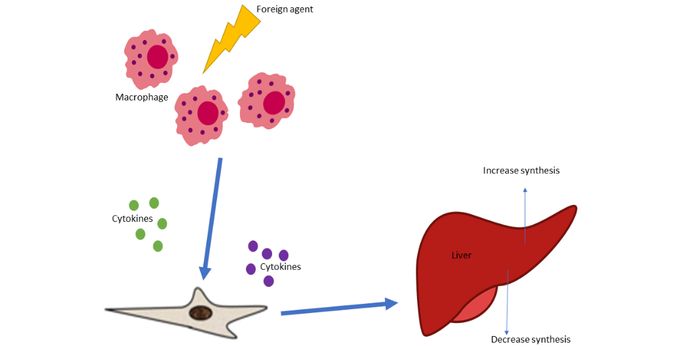

APR 22, 2016Health & MedicineMacrophages exist in every type of body tissue, in the lungs as alveolar macrophages and in the liver as Kupffer cells. ...